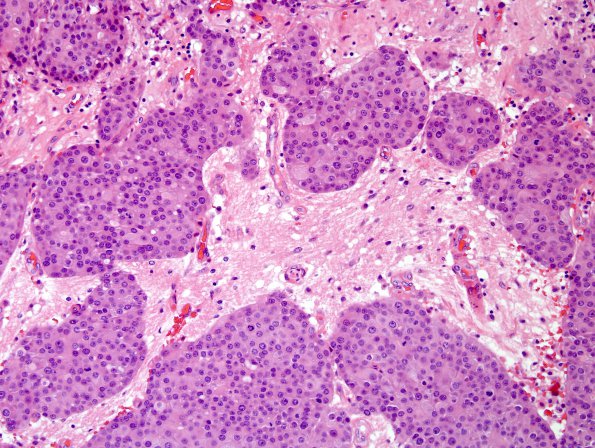

Washington University Experience | NEOPLASMS (METASTASES) | Microscopic | 84A1 Metastasis (Case 84) breast primary H&E 4.jpg

Case 84 History ---- The patient is a 54-year-old woman presented for an elective resection of her known left cerebellar pontine angle tumor. The patient's past medical history is significant for HIV infection. She had no prior malignancy. Brain MRI on 12/2013 showed a 4.0 cm left cerebellar pontine angle dural-based tumor. Operative procedure: Posterior fossa craniotomy for tumor resection. ---- 84A1-4 H&E stained sections from the posterior fossa mass show multiple fragments of a poorly differentiated high-grade neoplasm with high mitotic index, multifocal necrosis, and widespread brain invasion. The tumor cells are arranged in sheets, cords, and nests. Small tumor nests extensively infiltrate adjacent cerebellar parenchyma. Mitotic figures are abundant and reach 65 mitoses/10HPF. Necrosis is widespread and often with comedo-type morphology. Individual tumor cells are epithelioid with distinct cell borders, abundant eosinophilic cytoplasm, round nuclei, and prominent macronucleoli.